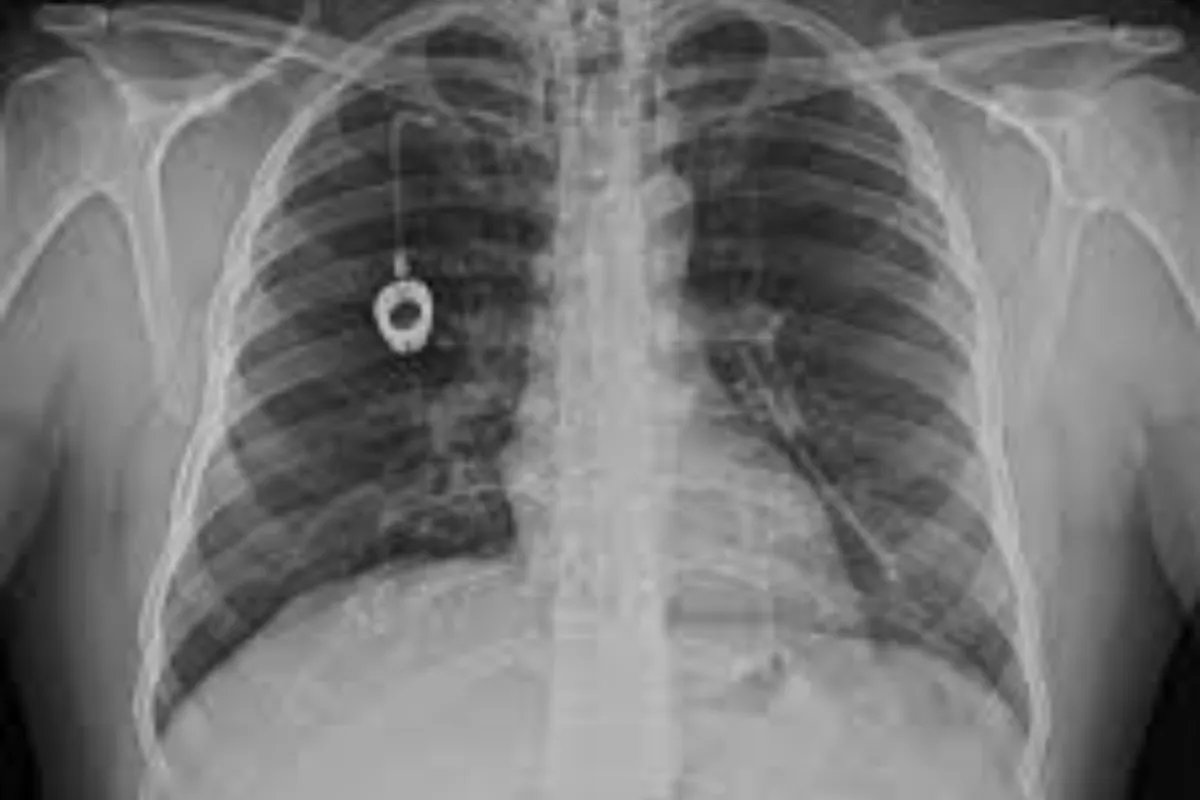

Peripheral Angioplasty procedure at Sarda Vascular Centre Dehradun

Interventional Radiology (IR) uses real-time imaging such as X-ray, ultrasound, CT, or MRI to guide tiny instruments through the body for treatment — without large surgical incisions.